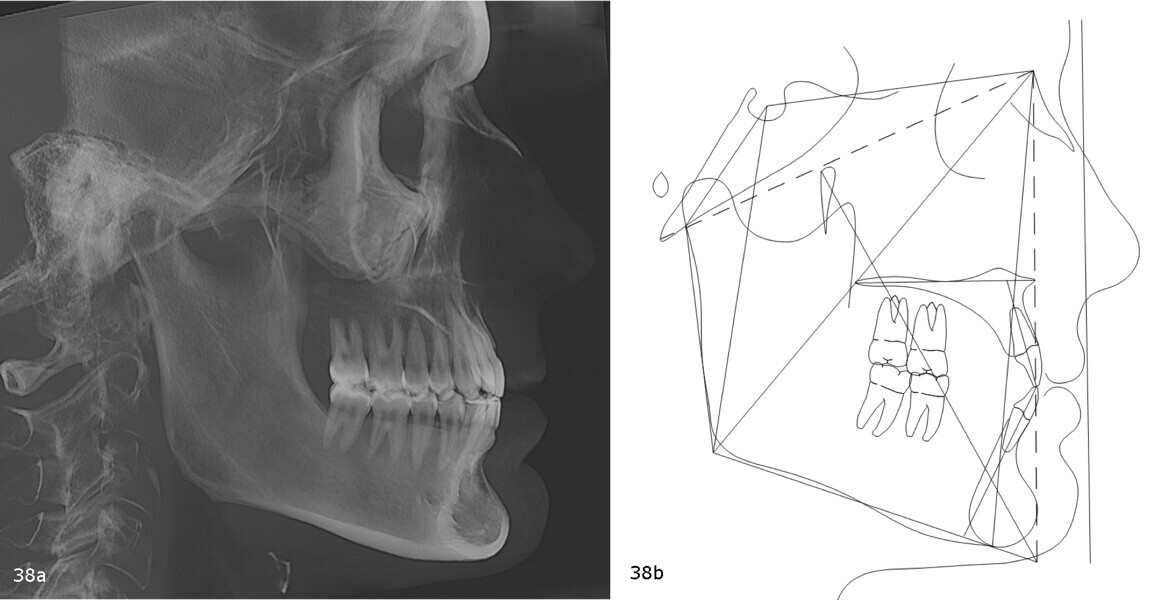

The panoramic radiograph revealed the absence of third molars and good root morphology and parallelism (Fig. 37). The cephalometric radiograph and tracing indicated a Class III skeletal pattern tendency, characterised by a short cranial base and a long mandible. The maxillary incisors were retroclined, and the mandibular incisors were proclined (Fig. 38).